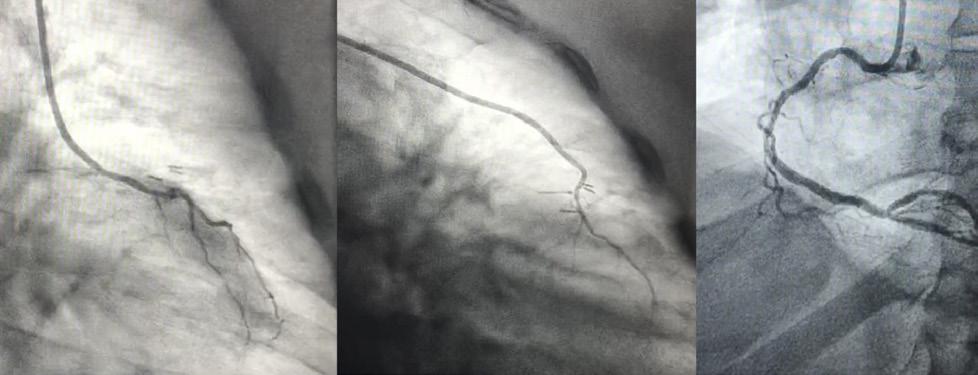

most technically challenging operations that a cardiac surgeon can learn and perform nowadays. Through a small incision, reconstructive microsurgery must be performed flawlessly, with a different exposure for the harvesting of each conduit, the sourcing of inflows, and the grafting of each myocardial territory. In our presentation, we highlight the techniques and results of less invasive CABG. We also propose a stepwise path to achieving safe, high-quality, reproducible, and durable forms of multiarterial MICS CABG. Ultimately, the close involvement of interventional cardiology colleagues to supplement the minimally invasive performance of robotic-assisted, bilateral internal thoracic artery harvest at MICS CABG effectively avoids the pitfalls of sternotomy, cardiopulmonary bypass, aortic manipulations, vein grafts, and incomplete or unvalidated myocardial revascularisation.

Coronary artery bypass grafting is the world’s most often performed cardiac surgery operation. However, CABG often remains as invasive today as it was 50 years ago. Minimally invasive coronary artery bypass grafting (MICS CABG) can take many forms and represents one of the